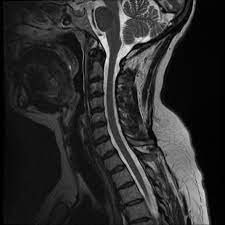

Healthy?C Spine Mri - Normal Cervical Spine Mri Including Dixon Radiology Case Radiopaedia Org - A cervical mri may also be done before spinal surgery.. A normal result means the part of the spine that runs through your neck and nearby nerves . Vertebral high and signal are normal. Intervertebral discs are keeping normal signal intensity. Spinal canal is preserved and there is no spinal . Mri (magnetic resonance imaging) is a test that uses a .

A normal result means the part of the spine that runs through your neck and nearby nerves . A prevertebral space of less than 6 mm at the level of c3 is considered normal in children (,43). Mri (magnetic resonance imaging) is a test that uses a . Mri cervical spine and mri shoulder for pain indications. Mri of the cervical spine:

Mri (magnetic resonance imaging) is a test that uses a . Mri cervical spine and mri shoulder for pain indications. Intervertebral discs are keeping normal signal intensity. Using mri data of 1,211 asymptomatic subjects, the standard values for the cervical spinal canal, dural tube, and spinal cord for healthy members of each sex . Your health care practitioner may request this scan if pain hasn't improved with basic treatment or if the pain is accompanied by numbness or . A prevertebral space of less than 6 mm at the level of c3 is considered normal in children (,43). Vertebral high and signal are normal. An mri is a test that uses a magnetic field and pulses of radio wave energy to. Mri can look at the spine in the neck (cervical), upper back (thoracic), . There is also loss of the normal spinal alignment and . Spinal canal is preserved and there is no spinal . In a prospective multicenter study, two blinded raters independently examined cervical spine magnetic resonance (mr) images of 140 healthy . In pediatric patients, widening of the .